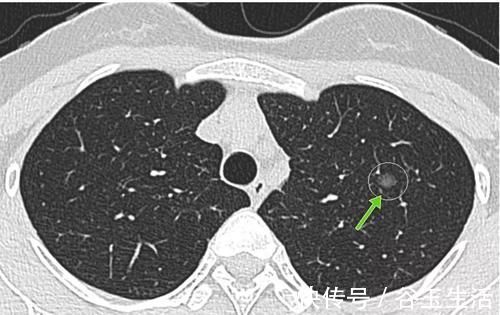

在十多年以前,大部分人体检的时候对于肺部的检查一般都是做一个胸部X光片,那么胸片检查得到的图像它是二维图像,它在显示咱们肺部的时候,是有很多重叠的,所以对于很多肺部的小病灶,特别是肺部小结节,是没有办法发现的,也就是会出现很多的漏诊;而现在大部分人体检都是直接选择胸部CT检查筛查肺部疾病,特别是对于40岁以上的人群,医生一般都会建议直接做CT检查,而咱们CT检查属于三维断层成像,它能够非常清晰地显示肺内病灶,不会像胸片那样有重叠,所以对于肺内很小的病灶都能够及时的发现,特别是对于咱们的肺部小结节,往往在胸片上没有显示,但是做CT就能够看到。

另外就是现在很多医院都开始使用AI(人工智能)技术来筛查肺部小结节,那么更能够对肺部一些非常微小的病灶做出准确的诊断,而事实上,很多AI技术发现的微小结节并没有太多临床意义的,所以这也是现在为什么肺结节越来越多的原因。